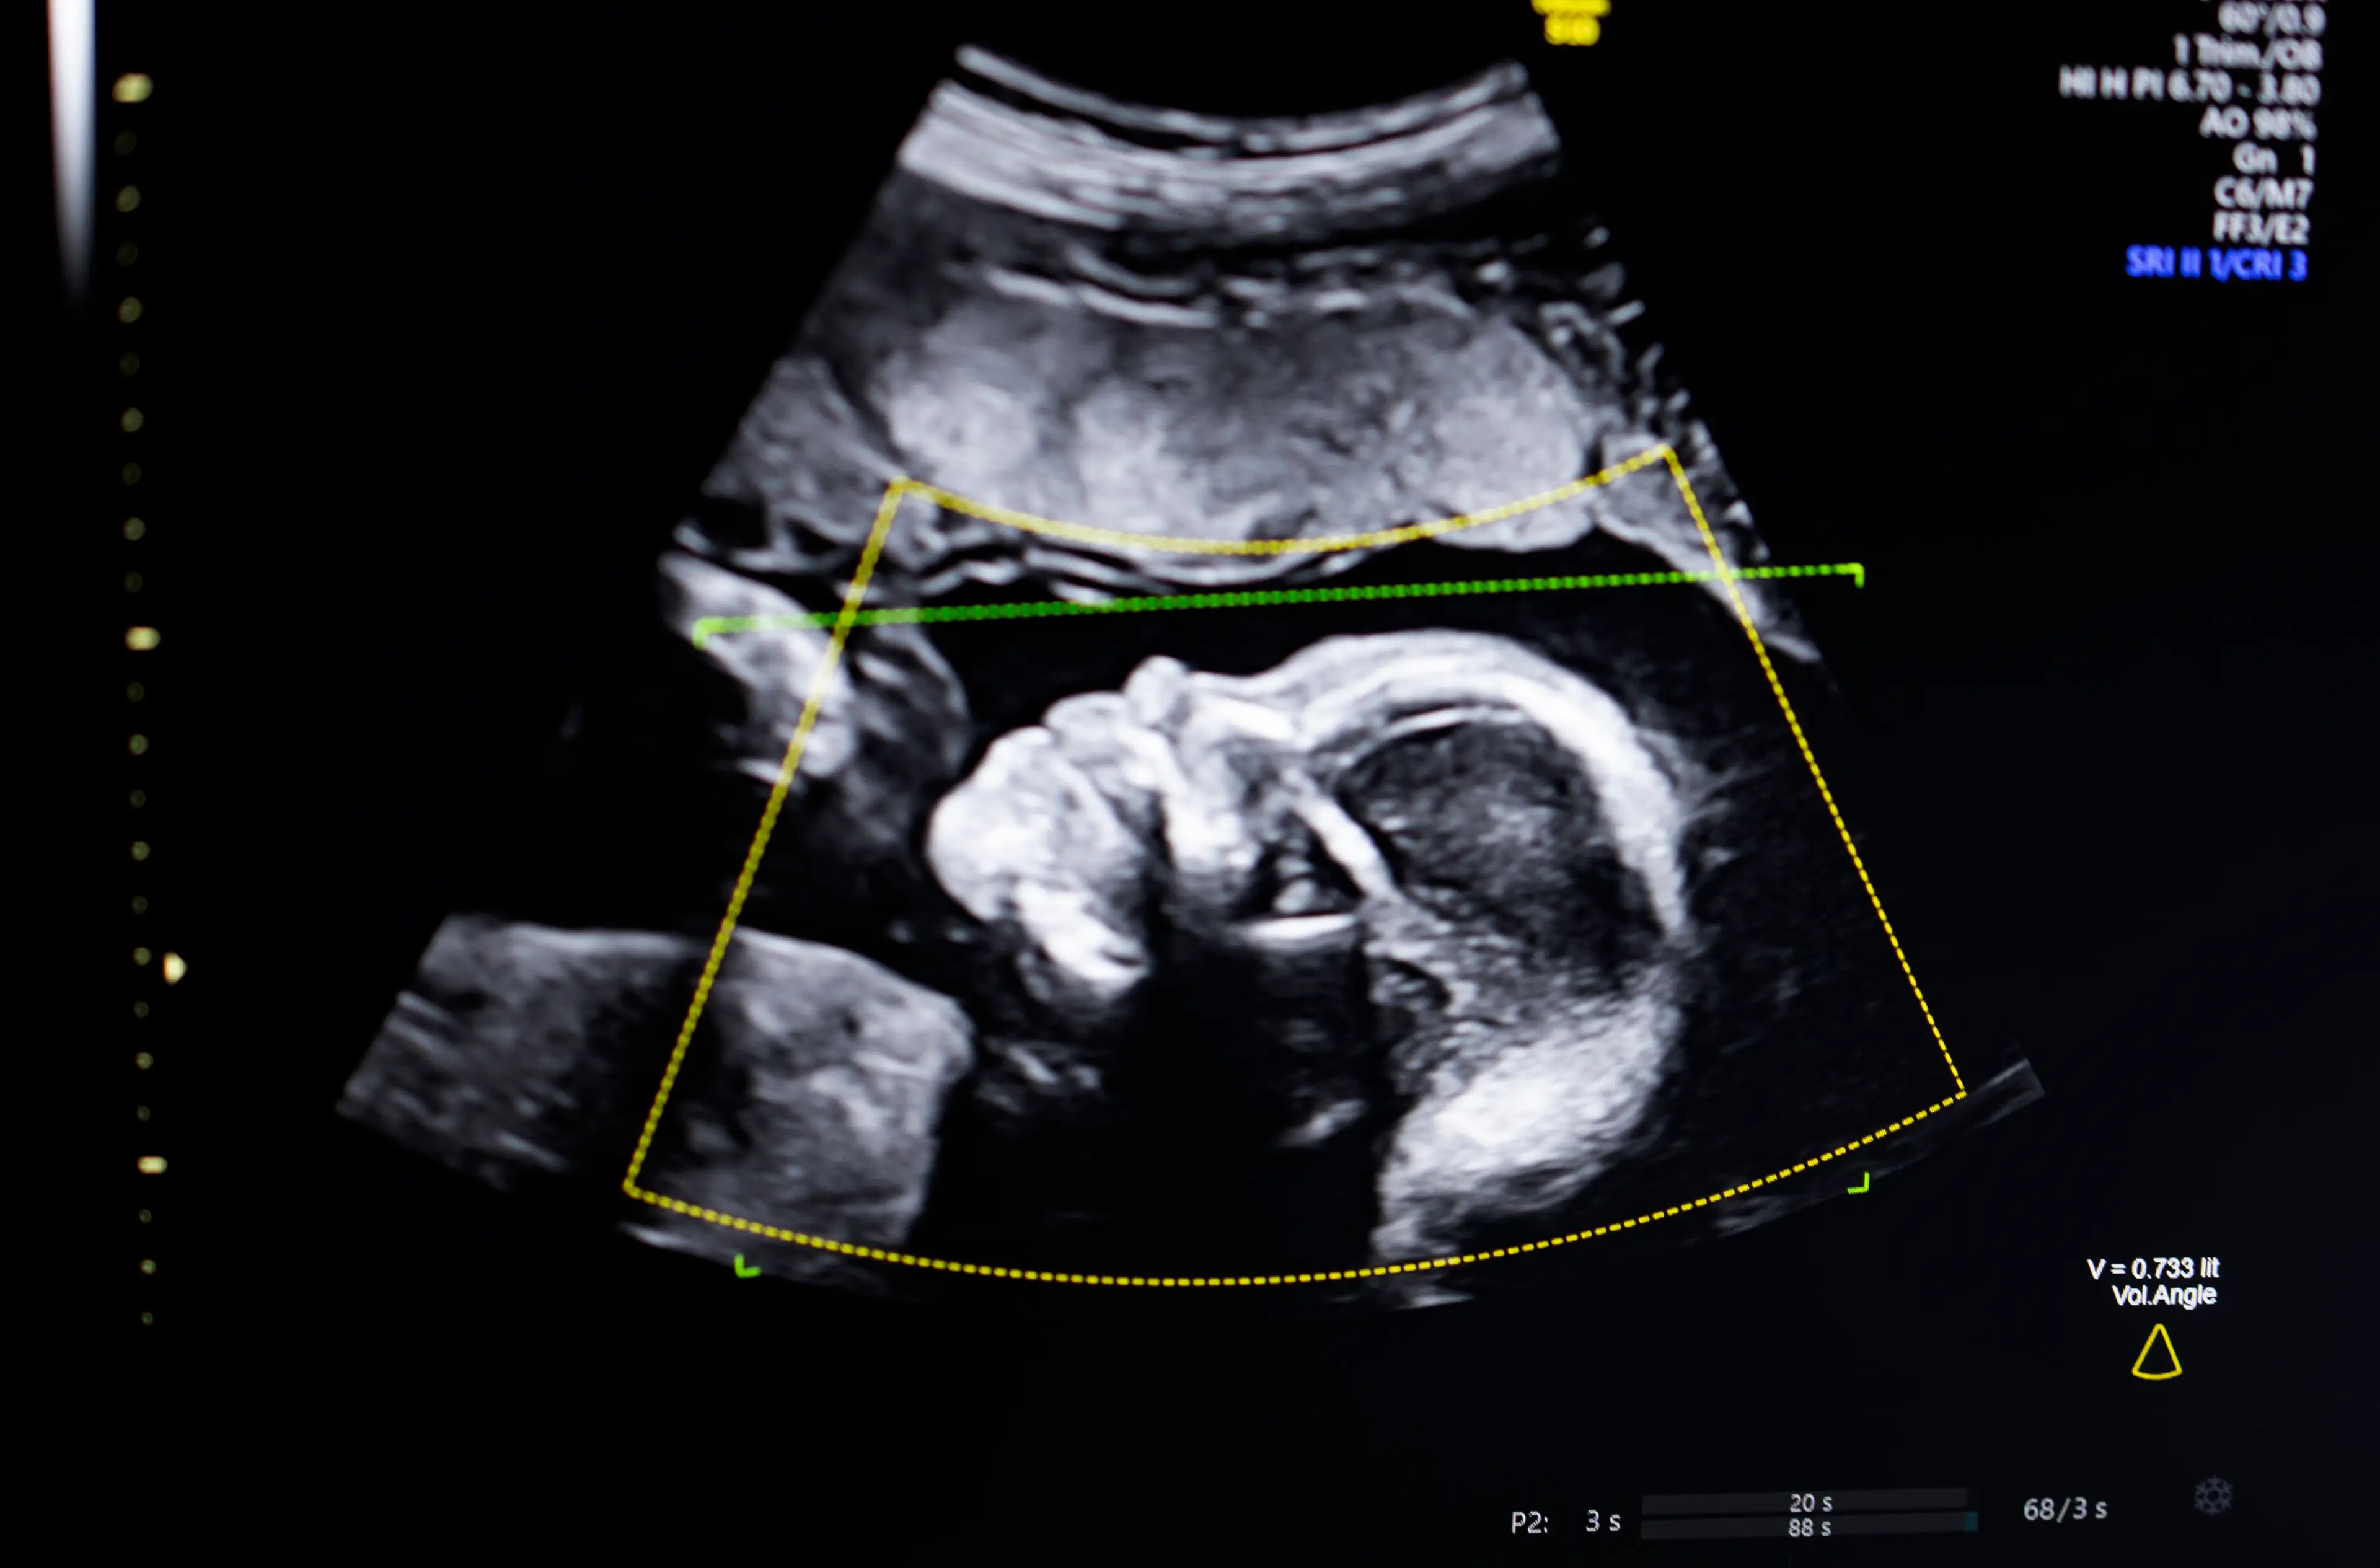

A groundbreaking new discovery could mean that in the future babies are born without biological mothers.

This is because scientists have discovered a new way to create human eggs from skin cells, meaning that a baby could potentially be created by two men, without any DNA needed from a woman.

It also has the potential to help women struggling to conceive have biological children.